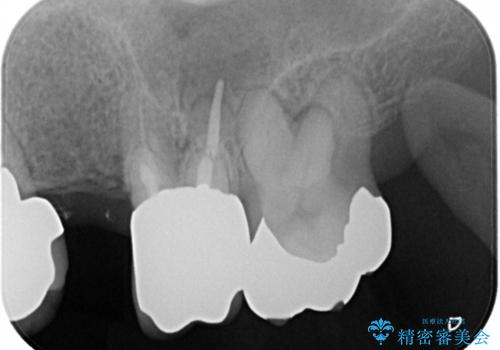

- 奥歯が痛いことを主訴にご来院された患者様です。入院してしまい、治療を2年間放置してしまったとのことでした。

左上は、抜歯とブリッジ治療を行いました(抜歯前に医師と対診)。

左下は、現在も抗がん治療を続けているため、観血的処置(インプラントなどの外科)はなるべく避けたいとのことで入れ歯を希望されました。それに伴い、入れ歯を支える歯のクラウンやりかえも行いました。

患者様はインプラント等の外科処置は希望されなかったため、セラミックと義歯で治療を行いました。